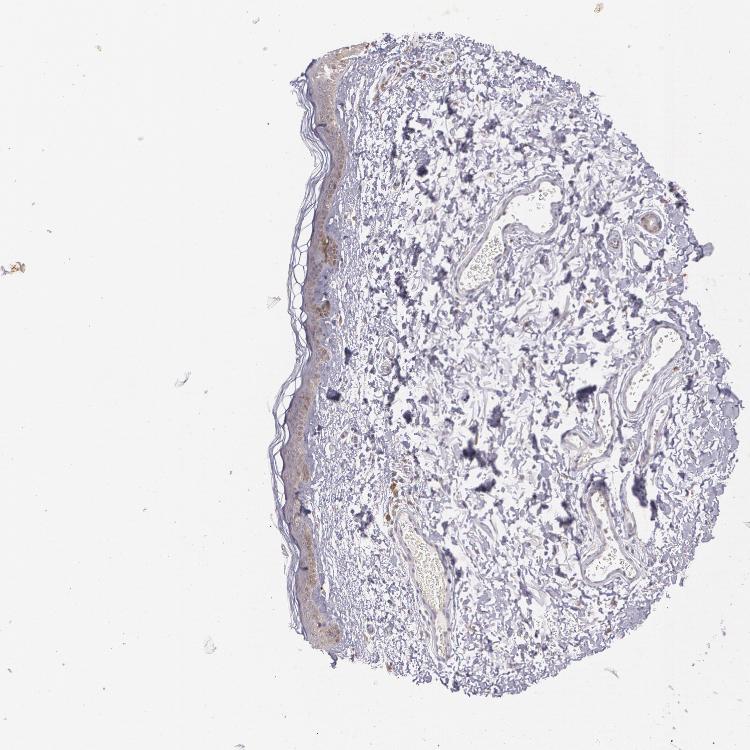

SKIN 1 - Antibody stainingi

Antibody staining in the annotated cell types in the current human tissue is reported as not detected, low, medium, or high, based on conventional immunohistochemistry profiling in selected tissues. This score is based on the combination of the staining intensity and fraction of stained cells.

Each image is clickable and will lead to virtual microscopy that enables deeper exploration of all samples and also displays staining intensity scores, fraction scores and subcellular localization as well as patient and tissue information for each sample.

Antibody CAB002583

Langerhans Low

Fibroblasts Low

Keratinocytes Medium

Melanocytes Medium

SKIN 2 - Antibody stainingi

Epidermal cells Medium